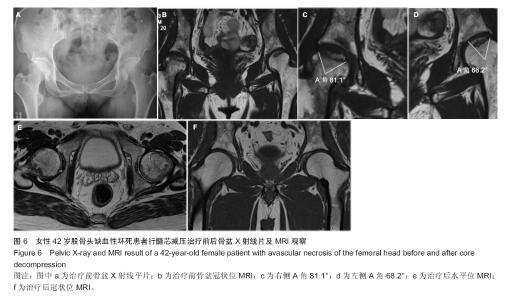

2.3 研究终点事件分析 经5年随访后,治疗组57髋,最终28髋行关节置换,髋关节置换率为49%,29例仍未行关节置换,即股骨头生存率为51%;对照组42例髋,其中29例关节置换,髋关节置换率为69%,13例未行置换,即股骨头生存率为31%,经行χ2检验后,P < 0.05,说明治疗组最终髋关节置换率明显低于对照组,差异有显著性意义,见表2。表3表明行髋关节髓芯减压术的患者明显延缓了行关节置换的时间,两组差异有显著性意义(P < 0.05)。对照组治疗后接受髋关节置换的高峰期为治疗后两三年,而治疗组治疗后接受髋关节置换高峰期为术后三四年,说明髓芯减压术确实有效的延缓了患者行髋关节置换的手术时间,两组之间的差异有显著性意义。"